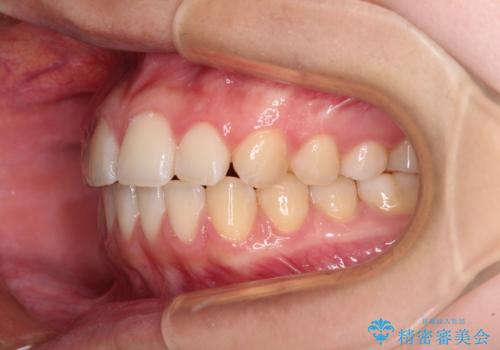

奥歯の咬み合わせを見ると、上顎が下顎に対して相対的に前方にあり、上下の前歯が接触していない状態でした。

咬み合わせを改善するためには、上顎臼歯を後方に移動させた咬み合わせにする必要があります。

奥歯の咬み合わせを改善しながら、並行してインビザラインで歯列を整えることとしました。